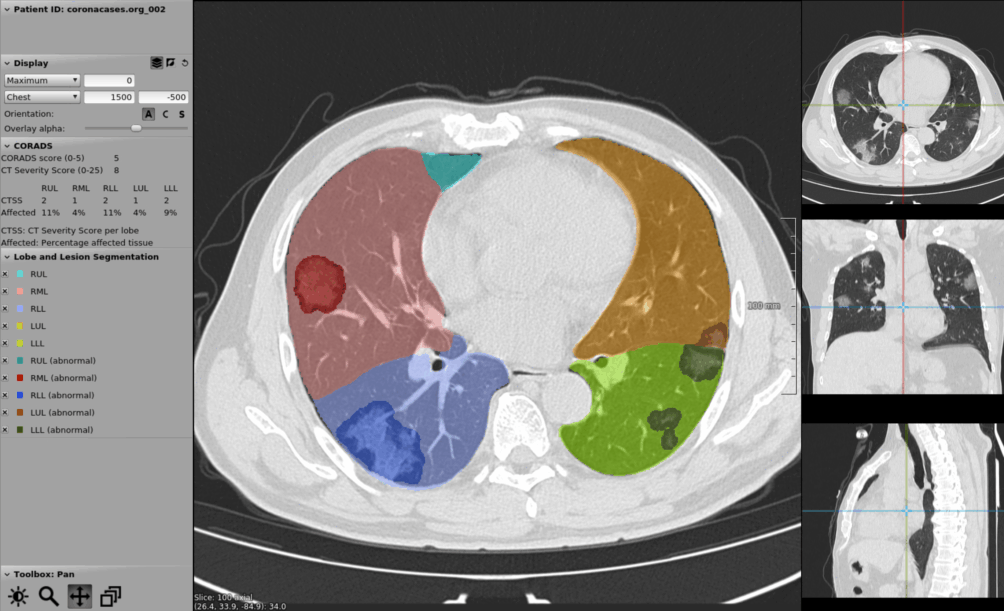

Within just a few months, Corads-AI – the algorithm that can estimate whether someone has COVID-19 – was ready for the market. Corads-AI is described in the leading journal Radiology and is made available free of charge during the pandemic via grandchallenge.org. “Corads-AI is widely used worldwide, particularly in North and South America, Europe, Asia, and Russia. Doctors can add their own CT scan and have it reviewed by the program.”

Although the course of the disease varies per patient, a CT scan of covid lungs is often surprisingly recognizable. “Pneumonia due to COVID-19 usually has a typical pattern with abnormalities at the edges of both lungs that is fairly easy to recognize with our algorithms.”